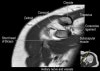

어깨 관절의 MRI 단면영상

- Coronal section

1) Supraspinatus, Inpraspinatus tendon

2) AC joint

3) Labrum(superior, inferior)

4) Biceps anchor, Inferior GHL, Axillary recess

5) GH joint cartilage

6) Osseous structure

7) Deltoid